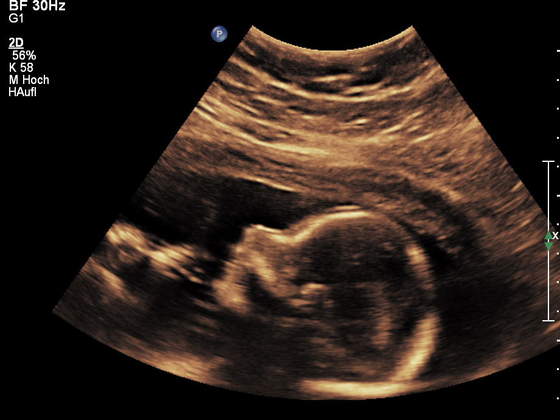

ja tez pochwale sie moim synkiem

jest podobny do swojego starszego brata